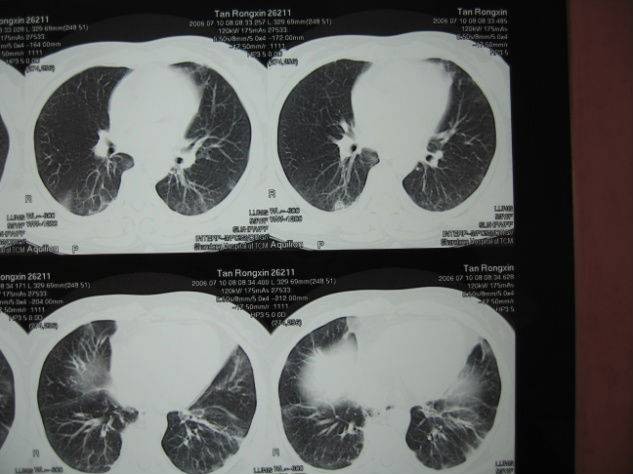

2周后(2006710日)复查胸部CT,炎症较前吸收好转,出院治疗。院外坚持应用百令胶囊、肺力咳胶囊、清开灵颗粒等。激素逐渐减停。随访至今(2013年)患者状况良好,活动无明显受限,生活质量无影响。

200667日治疗前

2006710日治疗后